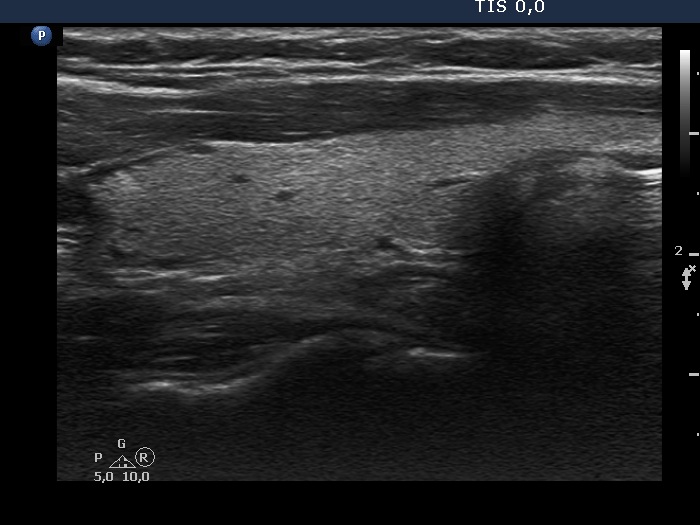

100 consecutive cases of papillary cancer - case 071 (ultrasonographic picture 12)

Left lobe, longitudinal scan.